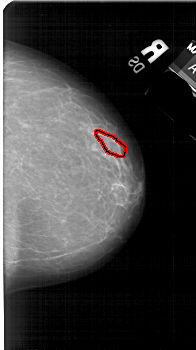

A_1548_1.LEFT_CC

LEFT_CC LINES 5356 PIXELS_PER_LINE 3136 BITS_PER_PIXEL 12 RESOLUTION 43.5 NON_OVERLAY

FILE: A_1548_1.RIGHT_CC.OVERLAY

TOTAL_ABNORMALITIES 1

ABNORMALITY 1

LESION_TYPE CALCIFICATION TYPE PUNCTATE DISTRIBUTION LINEAR

ASSESSMENT 3

SUBTLETY 1

PATHOLOGY BENIGN

TOTAL_OUTLINES 1

BOUNDARY